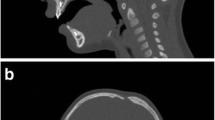

Calculating the intracranial volume

The entire intracranial cavity was considered region of interest (ROI) in order to calculate ICV. CT DICOM images were imported to OsiriX (version 7.0, Fondation OsiriX, Geneva, Switzerland) on Mac OSX. Start slice was considered just above foramen magnum and end slice just beneath vertex of the skull. On each axial slice, the ROI was manually outlined on the inner table of the skull, and defects were manually closed. The total ICV was extrapolated (Fig. 3).